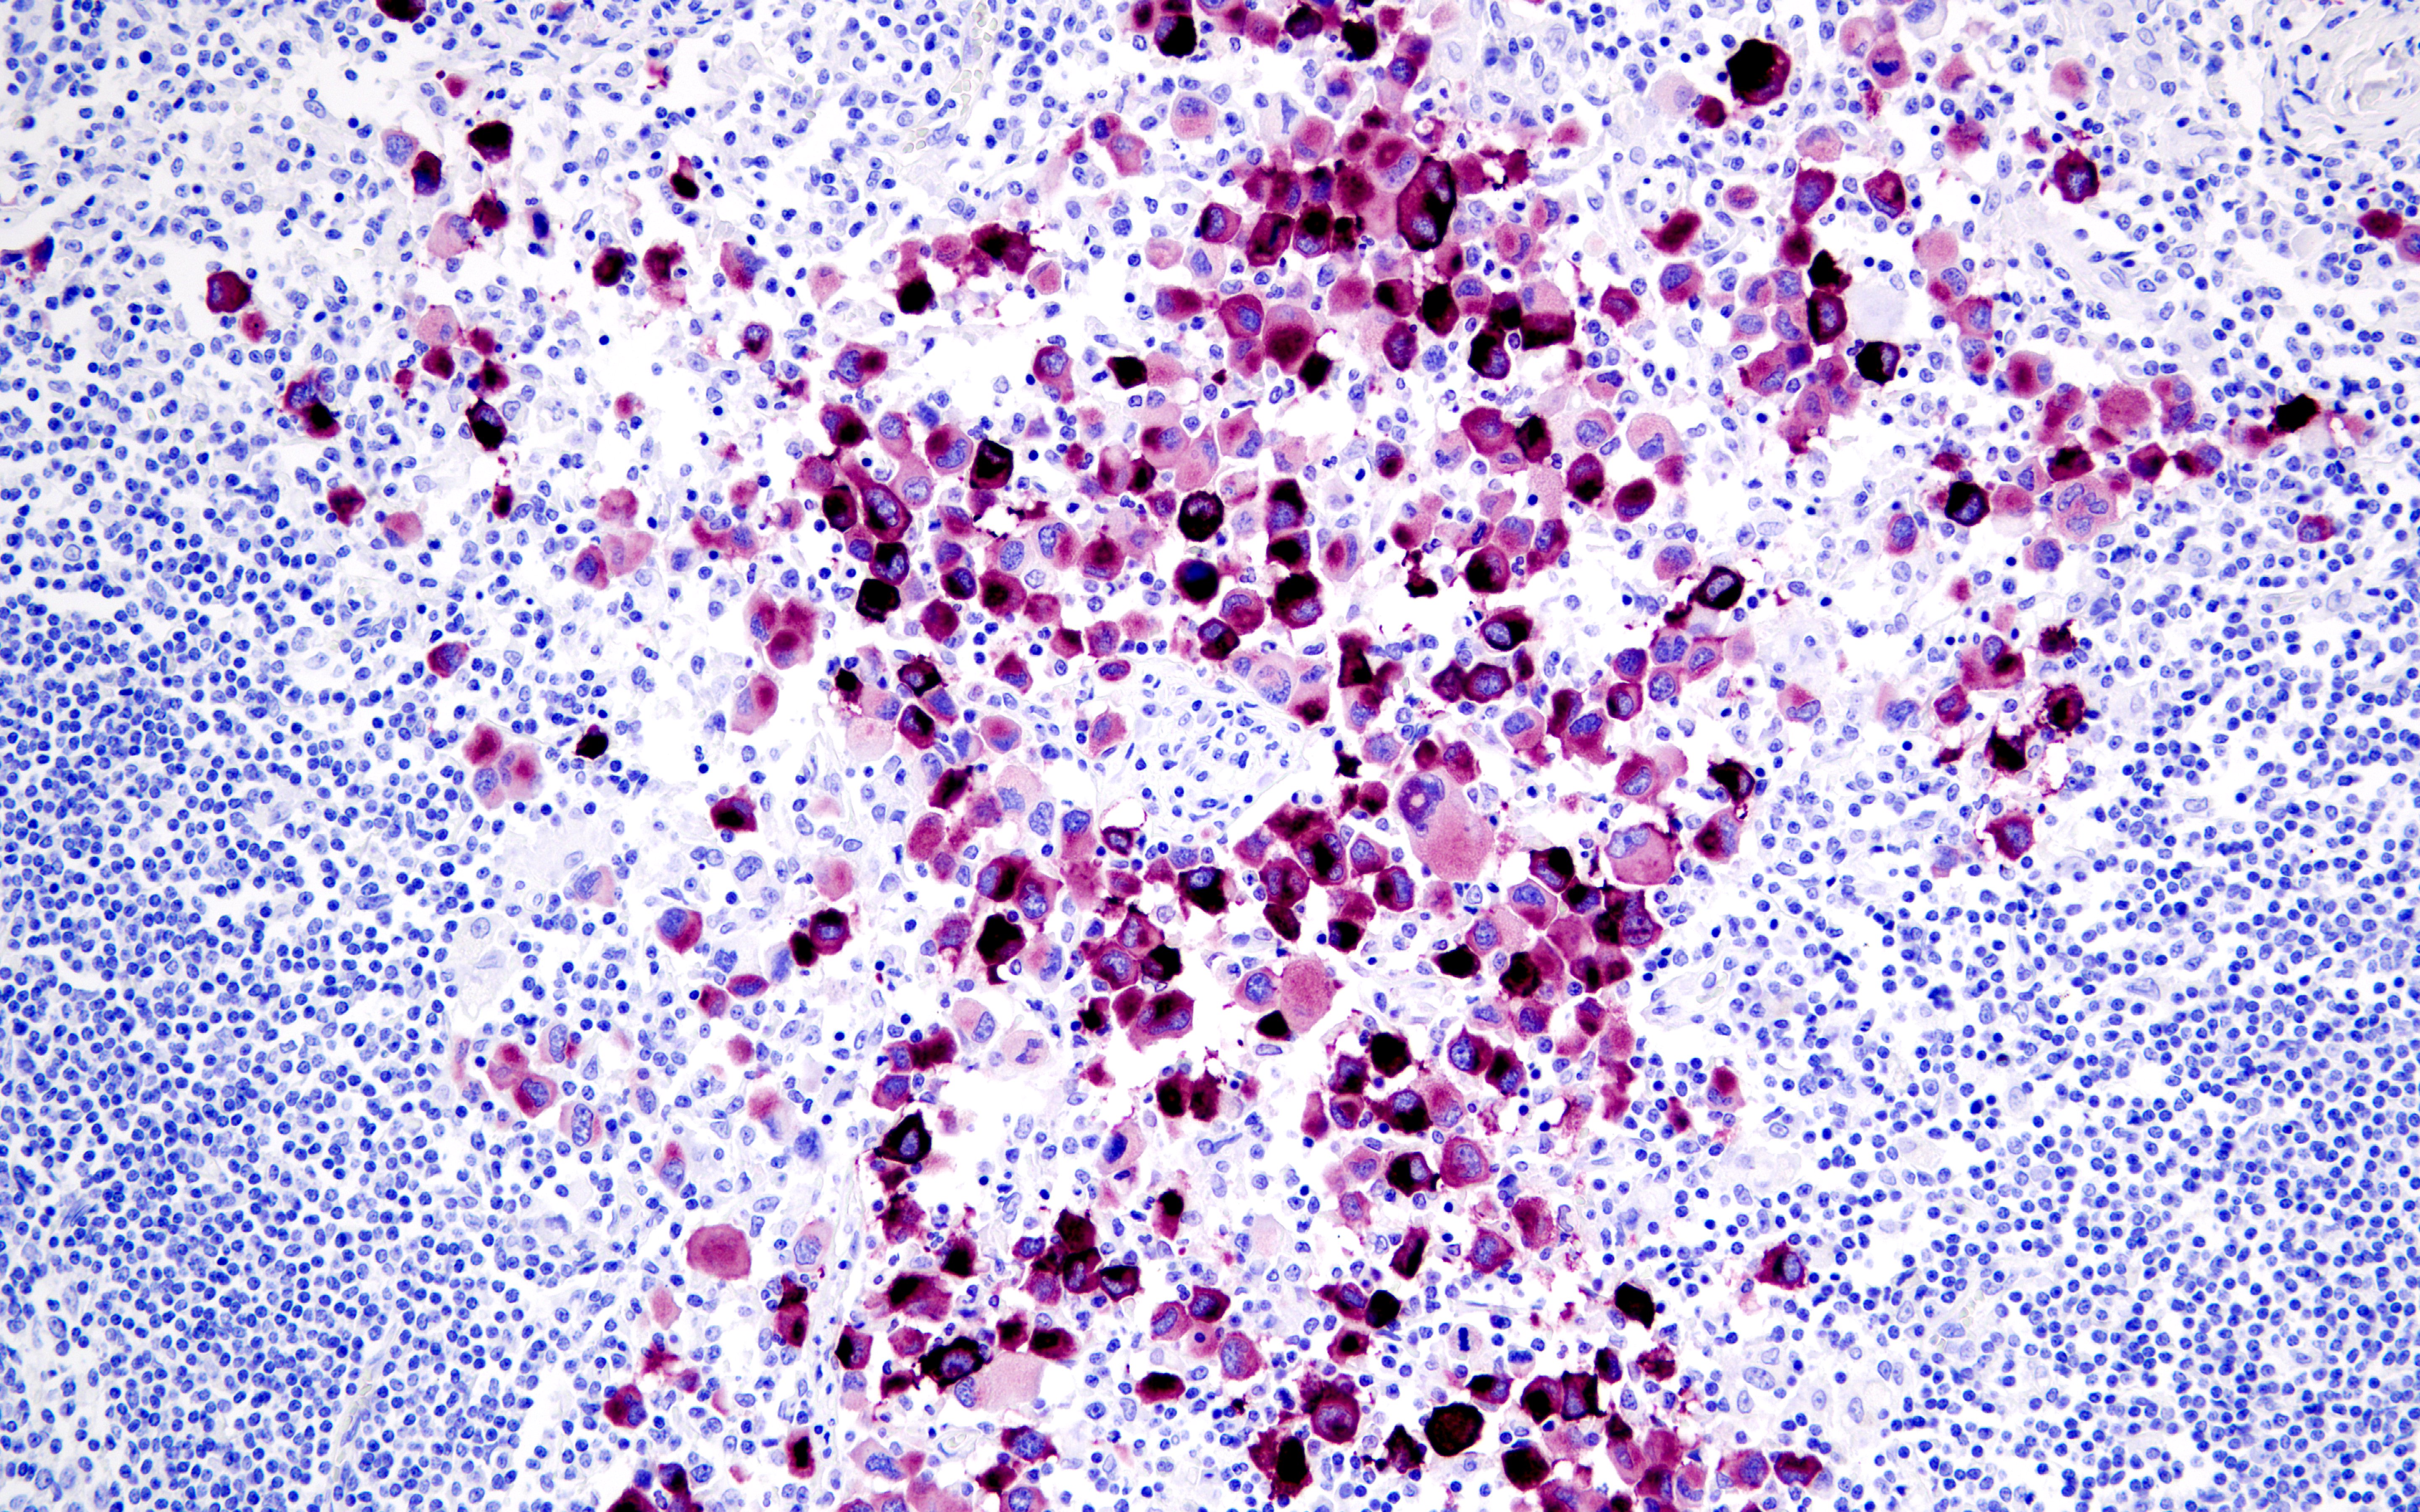

Multiplex IHC

Cat. #13684 | IHC, WB, IF, F

Critical immune checkpoint protein. Widely used in immuno-oncology research.

View Product